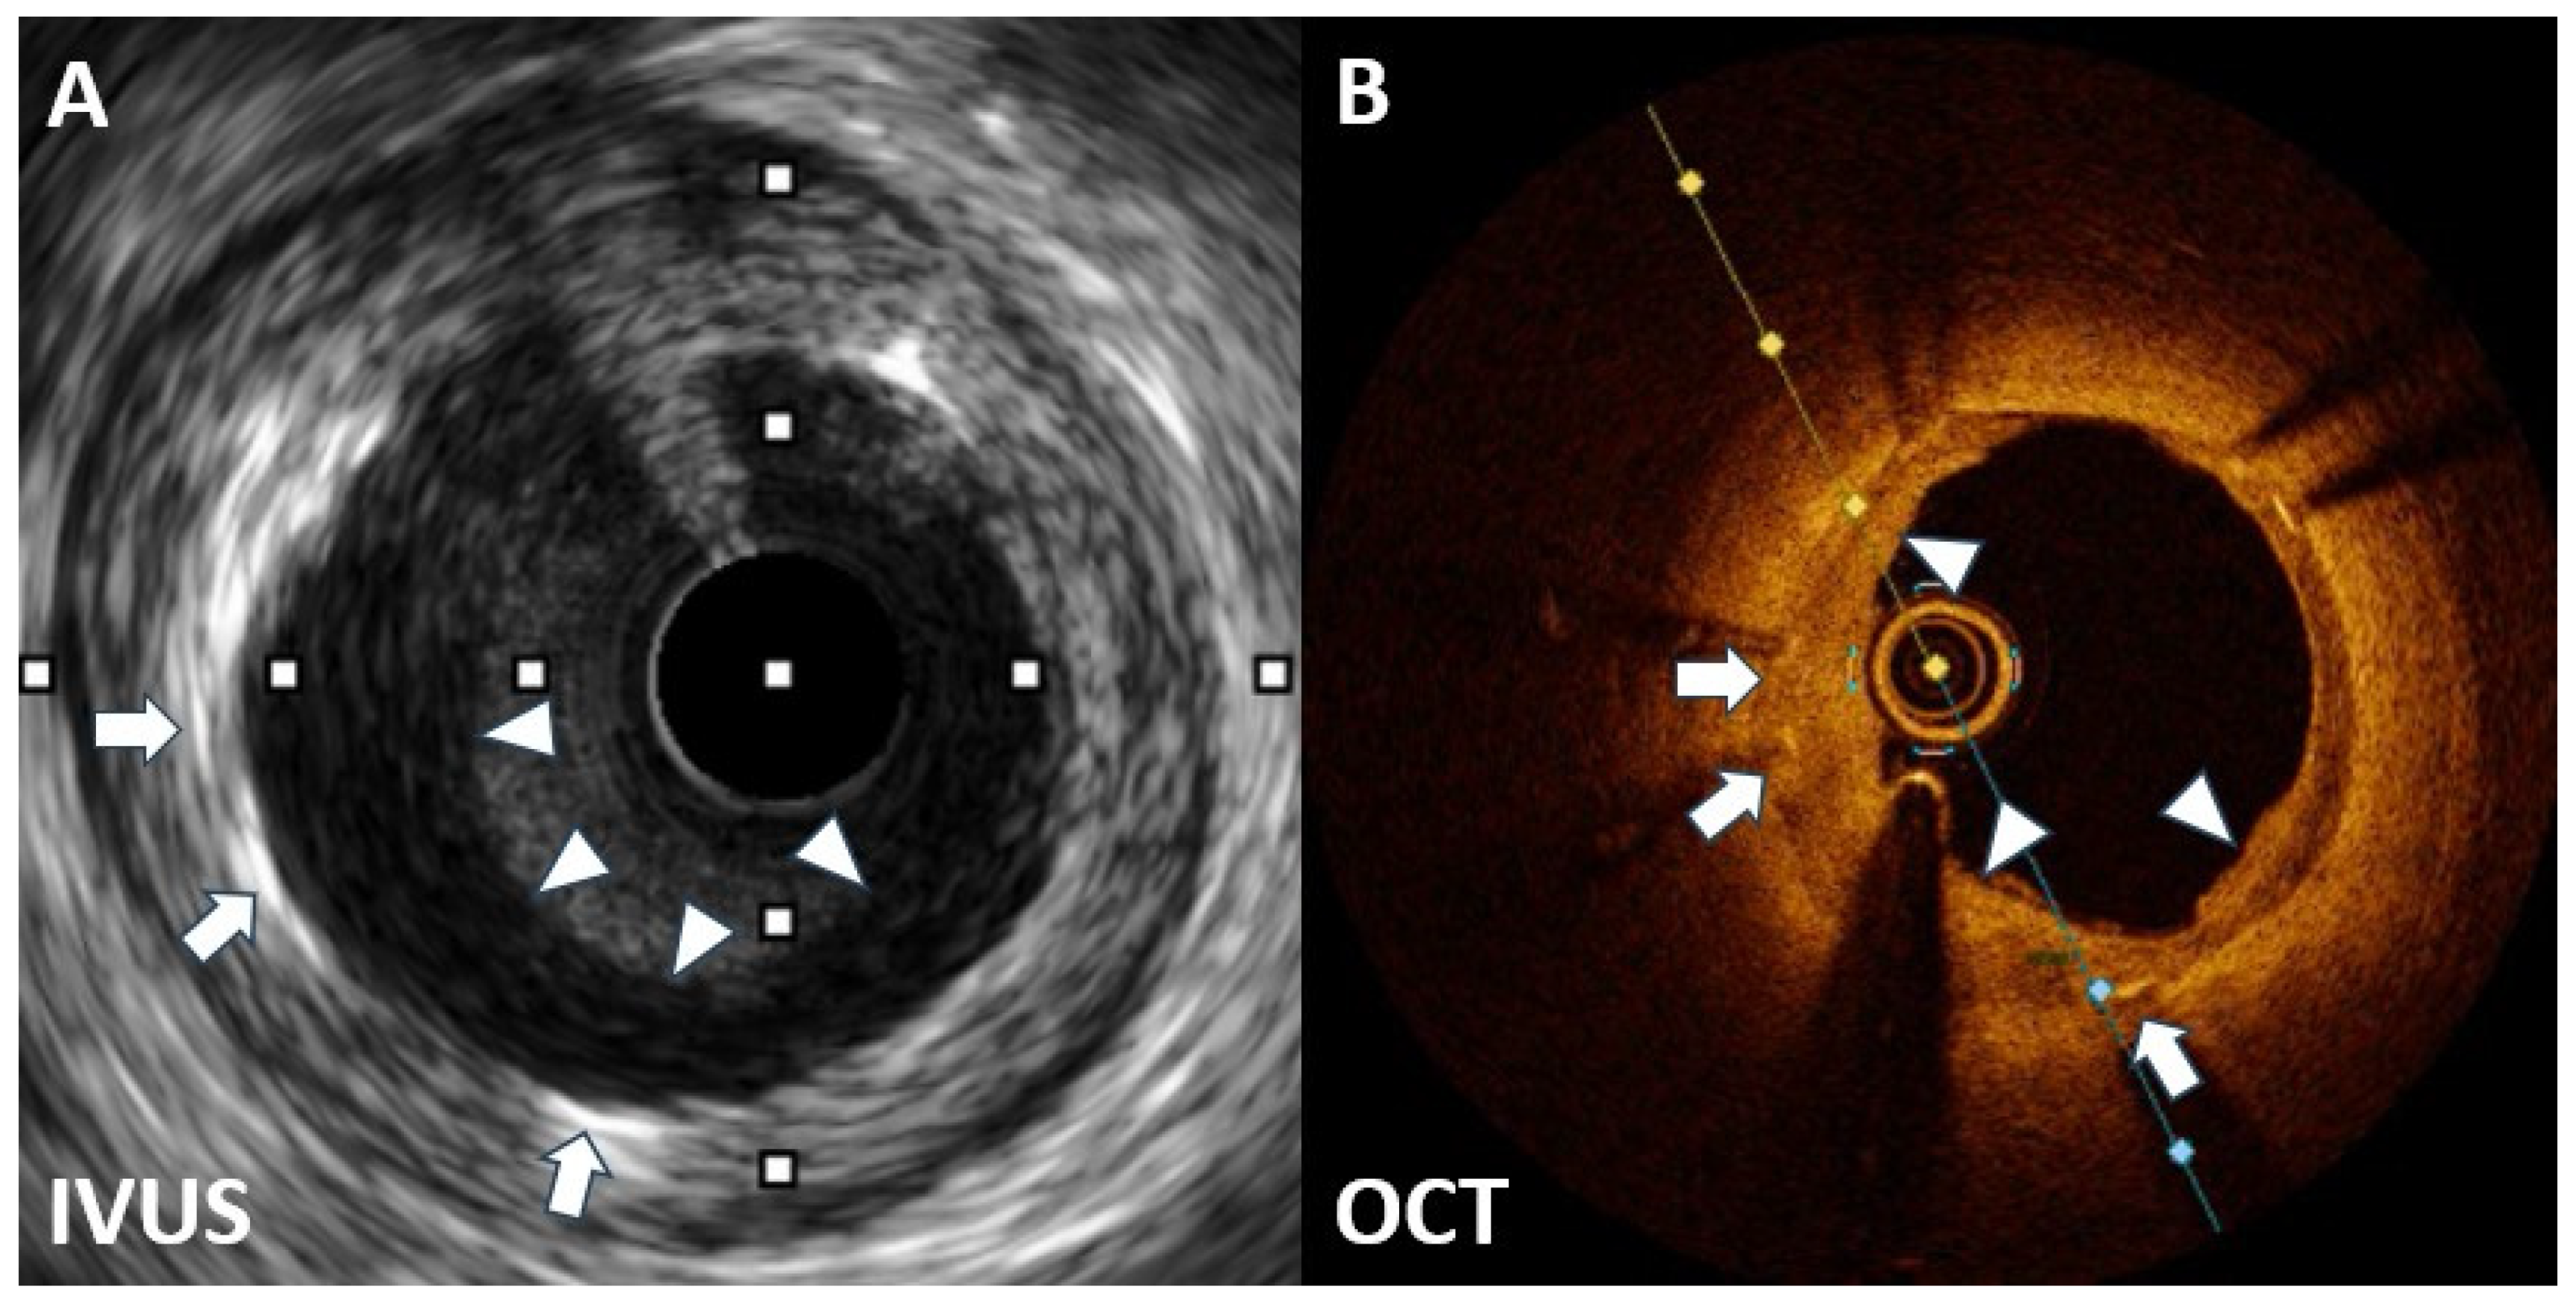

- Castagna, M.T.; Mintz, G.S.; Weissman, N.; Maehara, A.; Finet, G.; Waksman, R. "Black hole": Echolucent restenotic tissue after brachytherapy. Circulation 2001, 103, 778. [Google Scholar] [CrossRef] [PubMed]

- Hirose, M.; Kobayashi, Y.; Leon, M.B. Echolucent neointimal hyperplasia "dark wall" after sirolimus eluting stent implantation. Heart 2004, 90, 1143. [Google Scholar] [CrossRef] [PubMed]

- Goto, K.; Shiode, N.; Shirota, K.; Fukuda, Y.; Kitamura, F.; Tominaga, K.; Kato, Y.; Miura, H.; Inoue, K.; Nobuyoshi, M. Pathological finding of sirolimus-eluting stent (SES) restenosis lesion with black hole appearance on intravascular ultrasound. Circ. J. 2009, 73, 1969–1971. [Google Scholar] [CrossRef] [PubMed]

- Otsuka, Y.; Murata, T.; Kono, M.; Imoto, H.; Koyama, T.; Nakamura, K.; Kadama, S.; Noguchi, H.; Saito, T. Black hole restenosis after drug-eluting stent implantation for in-stent restenosis: Potential mechanism and optimal strategy. Heart Vessels 2015, 30, 682–686. [Google Scholar] [CrossRef] [PubMed]

- Kurita, T.; Terashima, M.; Suzuki, T. Serial optical coherence tomography imaging of the “black-hole” phenomenon by intravascular ultrasound following sirolimus-eluting stent implantation. EuroIntervention 2012, 7, 1480–1481. [Google Scholar] [CrossRef] [PubMed]

- Landmesser, U. Optical coherence tomography (OCT) evaluation after coronary stenting: The "black hole" and other low OCT signal-intensity areas. EuroIntervention 2012, 7, 1367–1371. [Google Scholar] [CrossRef] [PubMed][Green Version]